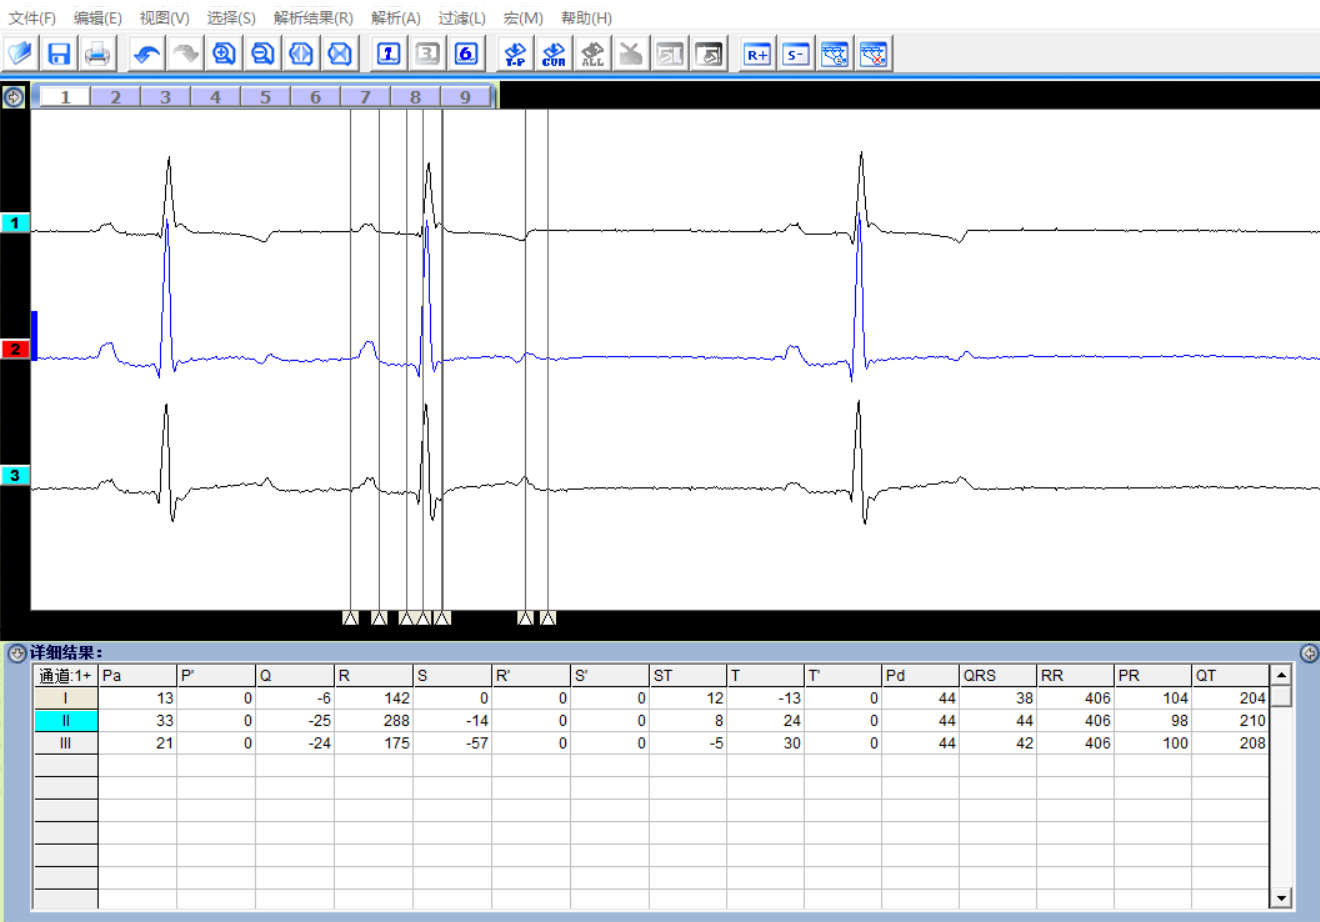

- 实时解析 I、II 导联心电信号,支持边采集边查看解析结果。

- 解析速度快,自动定位心电波段测量点(P波起点、P波终点、Q波起点、R波参考位置、S波起点、T波波峰、ST结合点),确保数据准确性。

- l 具有多参数解析功能,自动定位心电波段测量点(P波起点、P波终点、Q波起点、R波参考位置、S波起点、T波波峰、ST结合点),有助于提升数据可靠性。

- 由 I、II 导联推导出 3个导联(I、II、III)或 6个导联(I、II、III、aVL、aVR、aVF)。